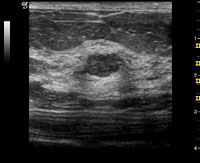

乳房エコー